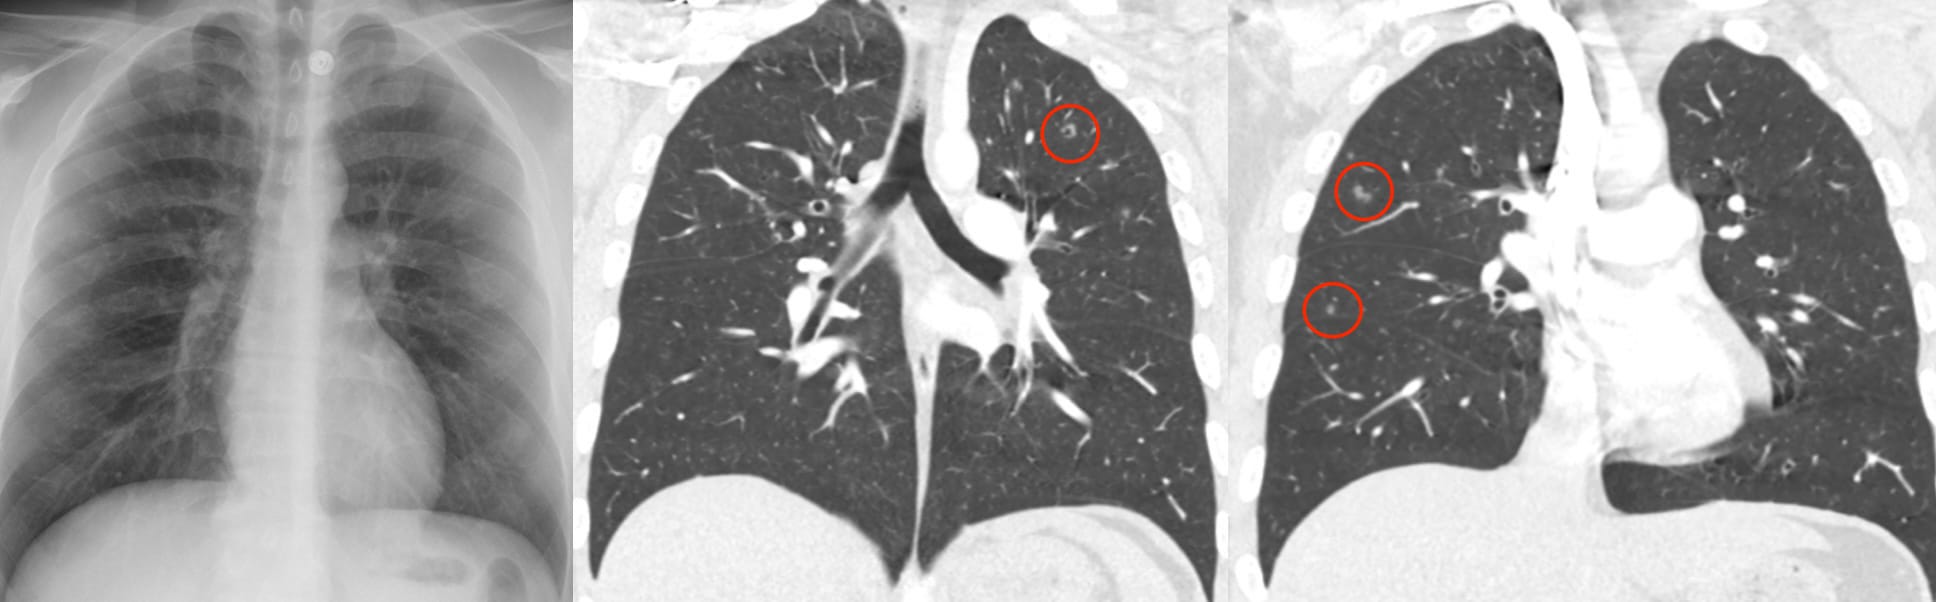

What are Langerhan’s Cells ?

The evolution of pulmonary histiocytosis (PLCH) accounts for the imaging findings:

Key Points

Note the predominant involvement of the upper lungs.

The very definition of an Aunt Minnie